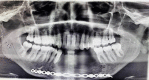

Destructive lesions in the craniofacial region especially in the jawbones, if associated with giant cells, include a spectrum of lesions that pose difficulty in diagnosis. The nature of such a lesion in the jawbones is questionable about whether it is a reactive/benign lesion or aggressive/non-aggressive. Clinical, radiological and histopathological correlation may be a reliable indicator to differentiate between the qualities of the lesion, which directly accounts for effective and individual planning of the treatment. Here we present a case of a woman in her late 20s with an unusual destructive lesion of the mandible.